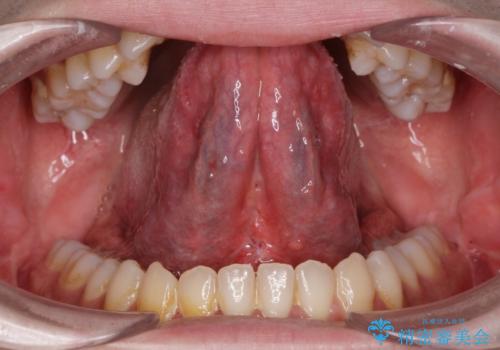

[滑舌を治したい] 舌の小帯の形成術

担当医 大元洋佑

![[滑舌を治したい] 舌の小帯の形成術の症例 治療前](https://seimitsushinbi.jp/wp/wp-content/uploads/2023/11/IMG_8451-500x350.jpg?v=1699614841)

![[滑舌を治したい] 舌の小帯の形成術の症例 治療後](https://seimitsushinbi.jp/wp/wp-content/uploads/2023/11/IMG_8901-500x350.jpg?v=1699614854)